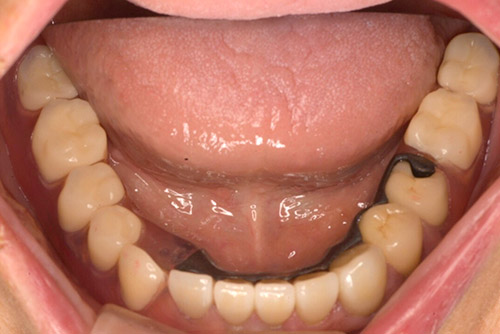

セラミッククラウン ノンクラスプデンチャー(チタン):60代 女性

治療前

治療後

| 治療名 | セラミッククラウン ノンクラスプデンチャー(チタン) |

|---|---|

| 患者情報 | 60代 女性 |

| 執刀医 | 大塚院長 |

| 治療内容 |

咬耗してしまった歯をセラミッククラウンで修復治療。 欠損部位はノンクラスプデンチャーを装着。 |

| 治療期間 | 7回 |

| 費用(税込) | セラミッククラウン:121,000円×5本 ファイバーコア:27,500円×5本 ノンクラスプデンチャー(チタン):660,000円 合計:1,402,500円 |

| 治療に対するリスク | ノンクラスプデンチャーは樹脂製のため柔らかさがあり、経年的に入れ歯の維持する力が緩くなる場合があります。 |